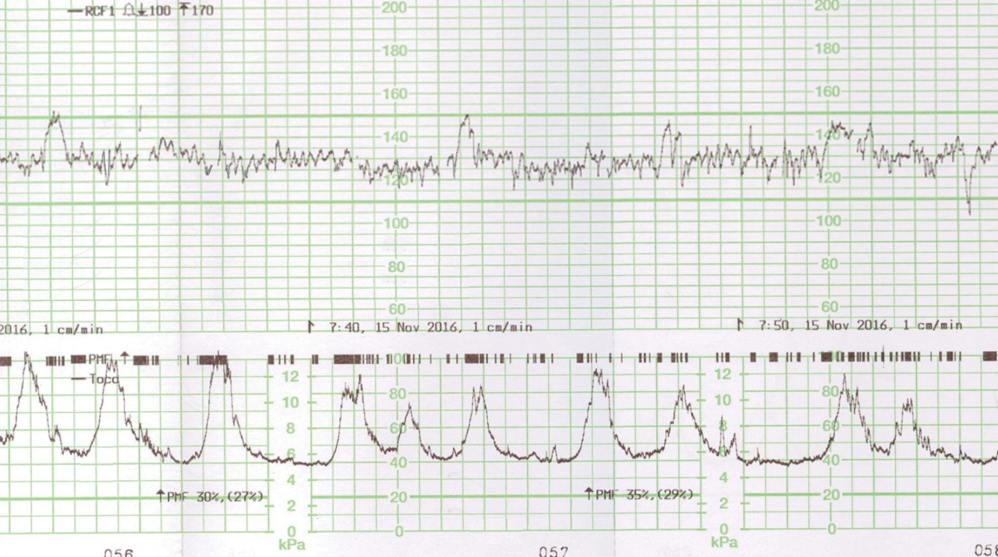

Il existe une franche cassure de la courbe, le fœtus est passé au troisième percentile. L’échographie en figure 1 est un écho-Doppler de l’artère ombilicale. Elle montre une diastole ombilicale nulle. Il s’agit donc d’un RCIU et non d’un fœtus petit pour l’âge gestationnel.

Concernant l’échographie de vitalité fœtale (figure 3), elle décrit :

– l’analyse du Doppler de l’artère ombilicale qui témoigne des échanges entre le fœtus et la mère (par ordre de gravité : diastole ombilicale positive normale ; diastole ombilicale nulle ; reverse-flow) ;

– l’analyse du Doppler de l’artère cérébrale moyenne qui peut mettre en évidence une redistribution cérébro-placentaire ou une anémie fœtale.